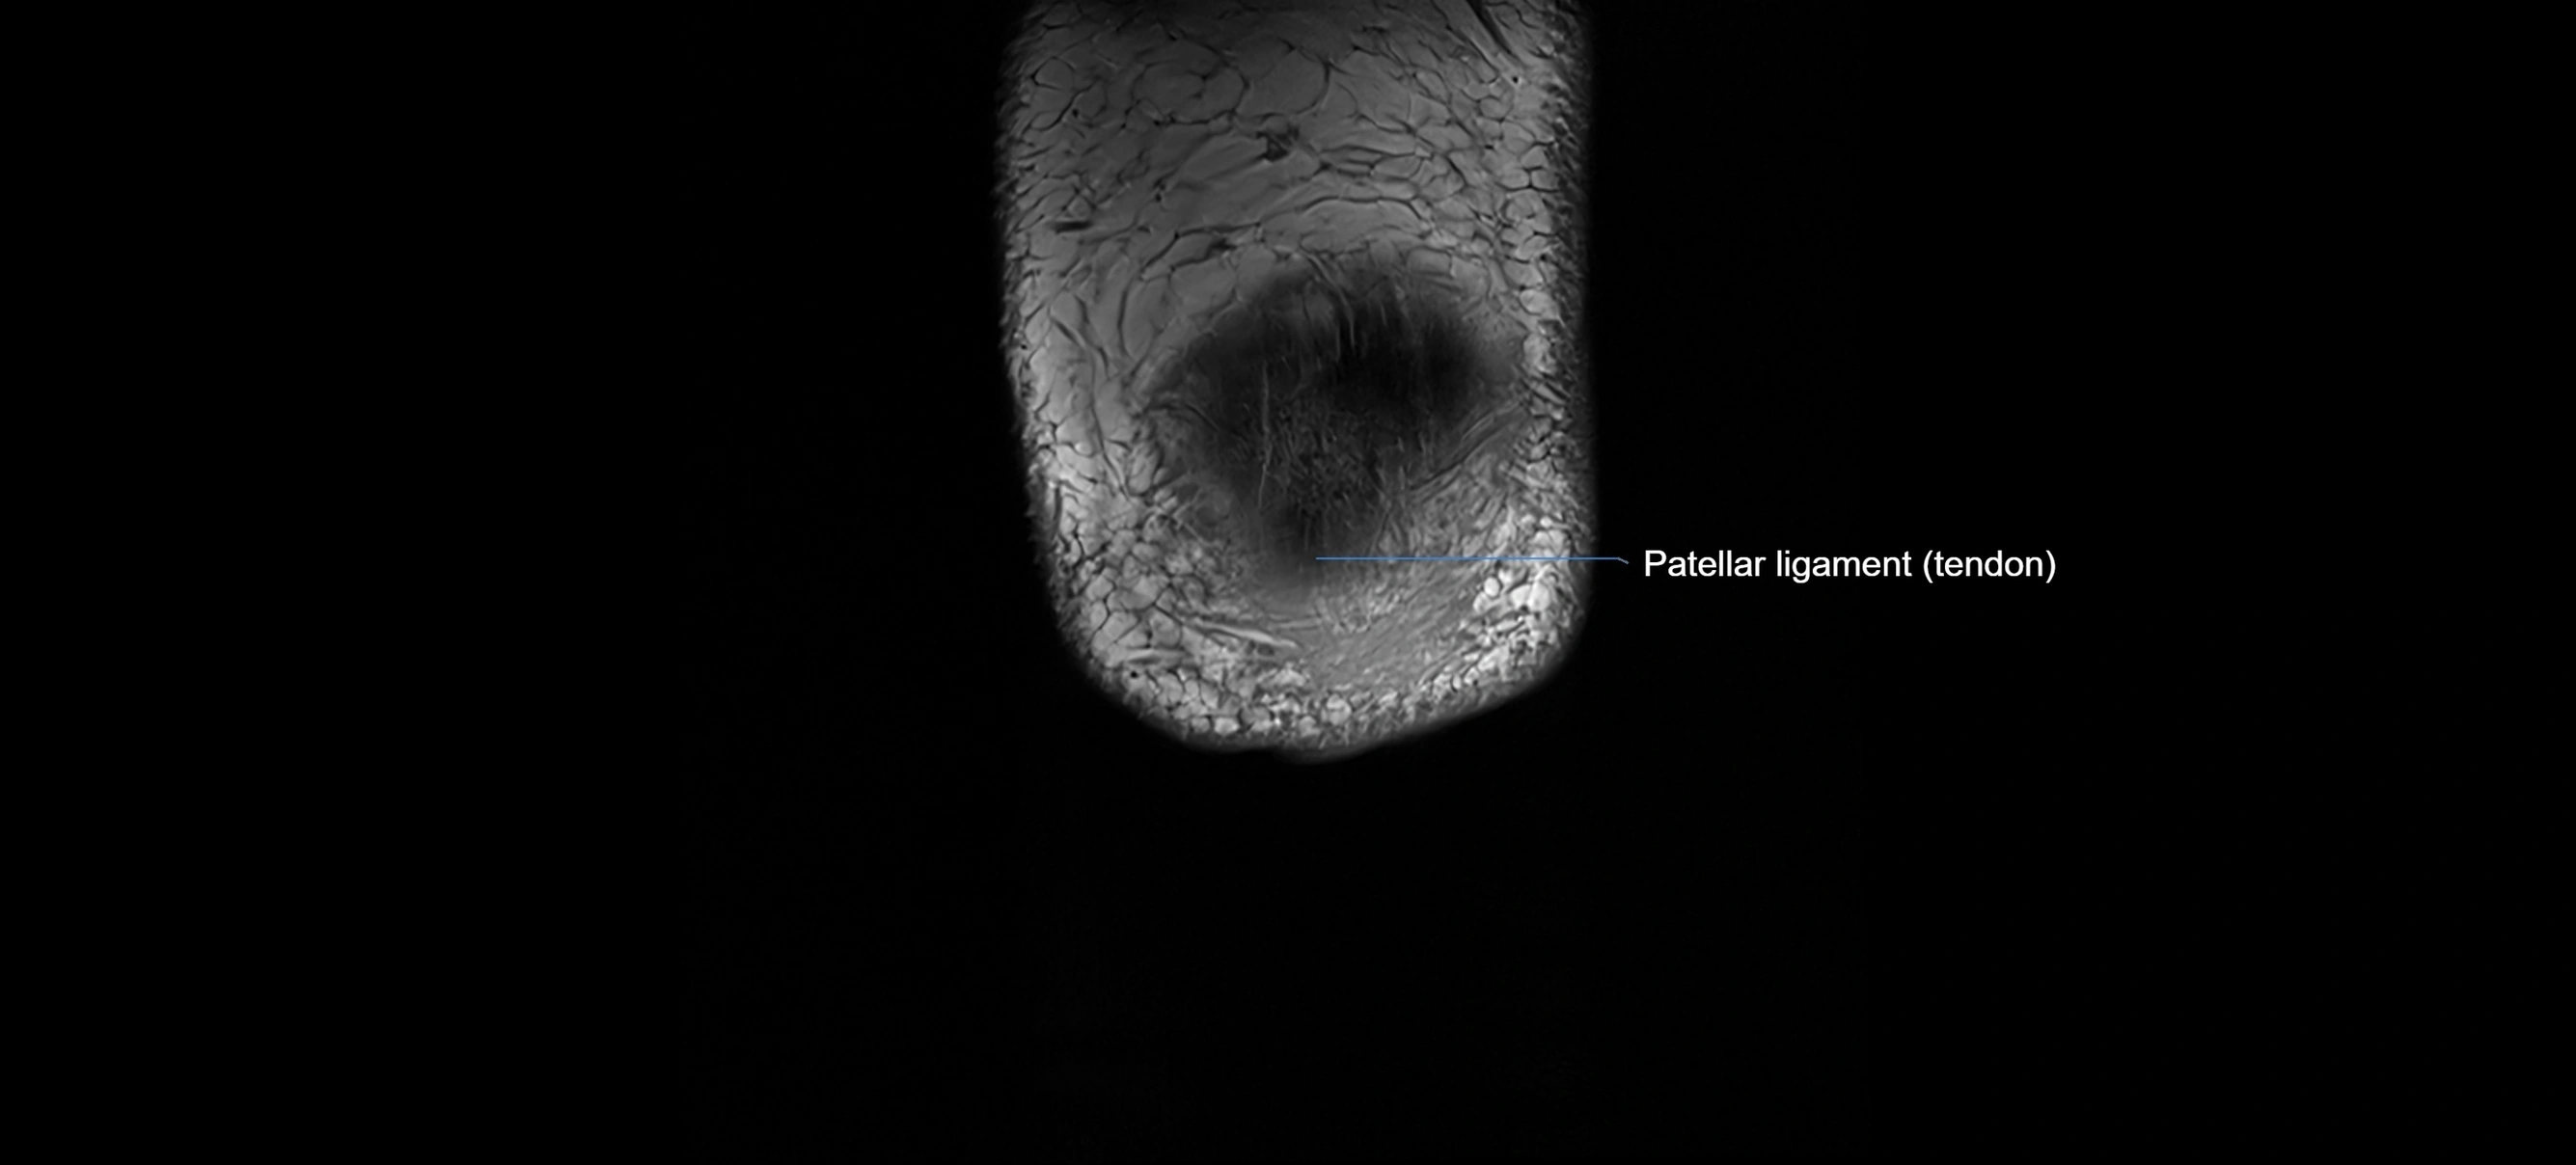

MRI images

image